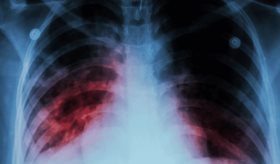

Hombre de 37 años sufre embolia pulmonar masiva en anestesia general durante laminectomía

Aunque suele presentarse en los periodos preoperatorio o postoperatorio, existen reportes de casos intraoperatorios. Las características fisiológicas alteradas bajo anestesia general pueden dificultar su diagnóstico y tratamiento inmediato.